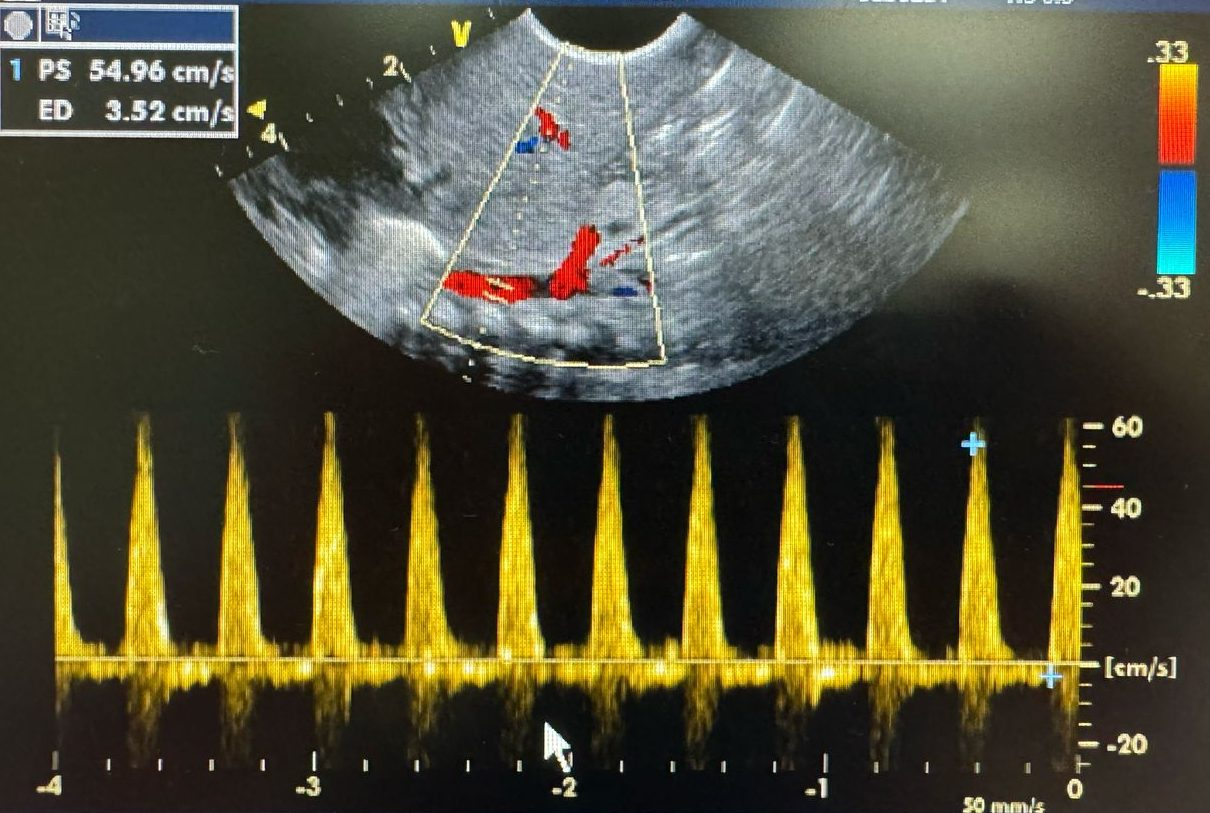

Velocidad del Flujo Sanguíneo: En neonatos prematuros, se ha observado un incremento en la velocidad sistólica del flujo sanguíneo desde aproximadamente 40 cm/s al nacer hasta 53 cm/s en la primera semana de vida. Este aumento se asocia con una reducción en la resistencia vascular renal y un incremento en la velocidad del flujo aórtico.[3]

DOPPLER RENAL DE ALTA RESISTENCIA Y FLUJO REVERSO EN UN PACIENTE CON PERSISTENCIA DEL DUCTUS ARTERIOSO CON REPERCUSION HEMODINAMICA.

SHOCK CARDIOGENICO SECUNDARIO A SOBRECARGA HIDRICA DEBIDO A PERSISTENCIA DE DUCTUS ARTERIOSO GRANDE